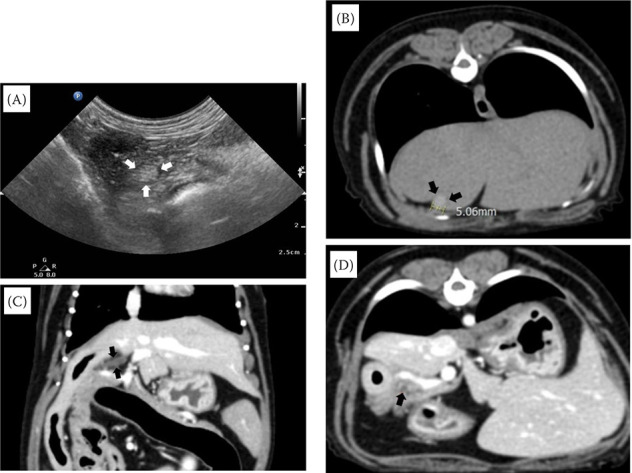

胆囊萎缩(GBA)的特征是胆囊的大小和体积缩小。在人类医学中,胆囊萎缩经常与影响胆囊和胰腺的病变同时发生,这一点已得到公认。然而,据我们所知,目前在兽医领域还很少有狗患胆囊炎的病例报道。在本研究中,我们报告了一例 7 岁约克夏梗犬患 GBA 的病例。腹部超声波检查和先进的成像技术(包括计算机断层扫描)证实了 GBA 的诊断,这些检查历时 4 年。患者最初主要表现为胃肠道症状,随后被诊断为胰腺炎并接受了治疗。与此同时,还发现了一个胆囊结节和一个疑似胆石症的异常结构。然而,在 4 年的随访中,胆囊结构消退,只剩下胆囊结节。值得注意的是,该患者没有进行胆囊切除术,除了胰腺炎相关症状外,在整个自发性萎缩过程中没有出现任何胆囊相关问题。基于这些发现,我们认为观察到的 GBA 很可能是由胆囊炎合并胰腺炎引起的。本病例强调了将 GBA 作为出现胰腺炎和胃肠道症状的犬科患者的潜在诊断的重要性。此外,它还强调了综合影像诊断在准确确定这些症状的根本原因方面的价值。

Gallbladder atrophy (GBA) is characterised by a reduction in the size and volume of the gallbladder. In human medicine, it is well-established that GBA frequently occurs together with pathologies affecting the gallbladder and pancreas. However, to the best of our knowledge, there is currently a dearth of reported cases of GBA in dogs within the veterinary field. In this study, we present a case report of GBA in a 7-year-old Yorkshire Terrier. The diagnosis of GBA was confirmed using abdominal ultrasonography and advanced imaging techniques, including computed tomography, which were performed over a 4-year period. The patient initially presented with predominantly gastrointestinal symptoms, which were subsequently diagnosed and treated as pancreatitis. Concurrently, a gallbladder nodule and an anomalous structure suspected to be cholelithiasis were identified. However, during the 4-year follow-up, the gallbladder structure regressed, leaving only the presence of the gallbladder nodule. Notably, cholecystectomy was not performed, and apart from pancreatitis-related symptoms, the patient did not show any gallbladder-related problems throughout the spontaneous atrophic process. Based on these findings, we propose that the observed GBA was likely induced by cholecystitis associated with pancreatitis. This case underscores the significance of considering GBA as a potential diagnosis in canine patients presenting with pancreatitis and gastrointestinal symptoms. Furthermore, it highlights the value of comprehensive diagnostic imaging in accurately determining the underlying cause of these symptoms.